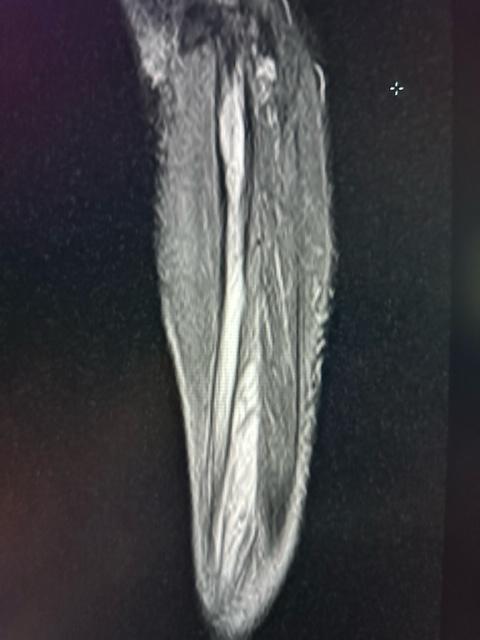

image2